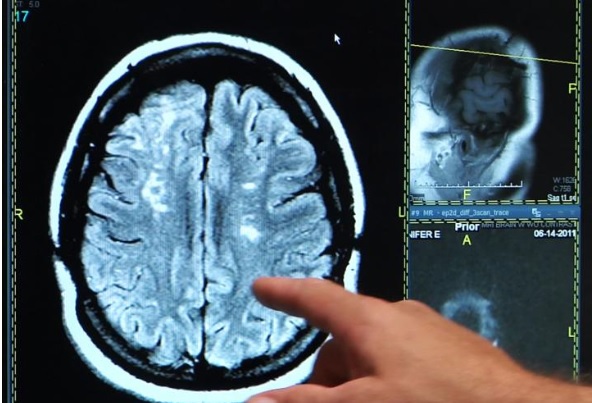

AVC : La molécule qui redonne de la plasticité cérébrale

Les chercheurs suédois administrent C3a ou un placebo à 28 souris, modèles d'AVC, une semaine après l'événement, et via des gouttes nasales. Les souris traitées récupèrent beaucoup mieux et plus rapidement : concrètement, elles sont capables d'utiliser à nouveau la patte paralysée par l'AVC. L'analyse montre également que C3a permet, en fait, la génération de nouvelles cellules nerveuses et la création de nouvelles synapses entre les cellules. Un processus que beaucoup considèrent comme clé pour la récupération de la fonction cérébrale.